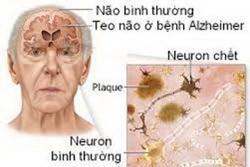

Những điều cần biết về bệnh Alzheimer

Alzheimer là một bệnh thoái hóa thần kinh gây ra hội chứng mất trí nhớ, ảnh hưởng tới hơn 30 triệu người trên toàn thế giới và đến nay vẫn là căn bệnh chưa có thuốc chữa. Sau đây là những điều cần biết về căn bệnh này nhân Ngày Alzheimer Thế giới (21/9).